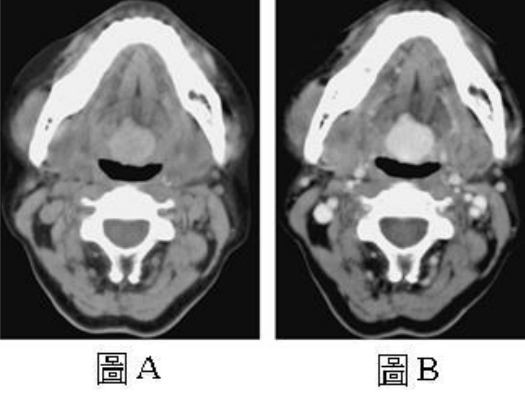

72.30歲女性患者,主訴咽喉有腫脹(fullness)的感覺,接受電腦斷層檢查,圖A為未注射顯影劑的影像,圖B則為注射顯影劑後 的影像,下列何者是最可能的診斷?

(A)舌根癌(tongue base cancer) (B)血管瘤(hemangioma) (C)舌甲狀腺(lingual thyroid) (D)轉移(metastasis)